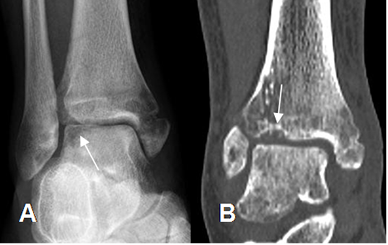

Fig 42. Artropatía neuropática. Patrón atrófico.

A: Rx AP y B: TAC reconstrucción coronal. Fractura del maléolo interno, con osteopenia del tobillo y lesiones osteocondrales de la tibia y el talo.